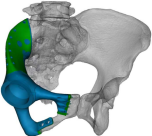

术前截骨规划

3D打印假体设计

据主刀医师徐生林介绍,本例病例将整个右侧半骨盆Ⅰ+Ⅱ+Ⅲ+Ⅳ区(累及骶骨)进行整块切除,同时切除肿瘤覆盖的部分骶骨。3D打印假体所有骨接触界面均设计为骨整合结构,有利于骨长入和骨盆假体的永久稳定。耻、坐骨结构不规则,因此设计组配式结构,有利于术中操作,极大地方便了术中的假体安装。

3D打印技术的出现,使骨肿瘤的精准切除成为了可能,3D打印制造技术能够很好地适形匹配肿瘤切除后的骨结构,通过假体-骨接触面的特殊制造技术达到假体-骨整合,解决了骨肿瘤切除后大段骨关节缺损的重建问题,在生物力学重建和功能重建上比常规假体优势明显。3D打印假体使骨肿瘤切除重建进入“个性化、精准化、私人定制”时代。